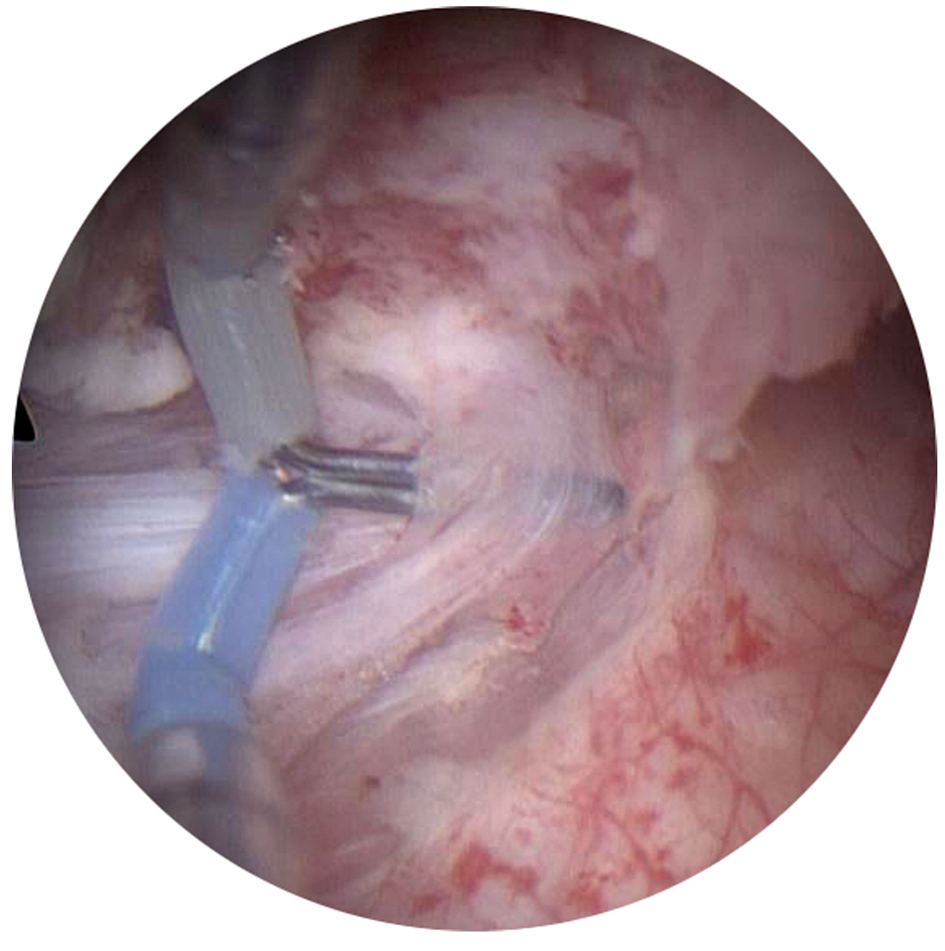

Senior consultant urologist with experience of TURBT performed all the resections under subdural anesthesia. No ONB was used. Patients were placed in the lithotomy position. The procedures started with a comprehensive cystoscopy, determining the presence, size, and location of all existing tumors. After electrocautery of the bladder mucosa 1 cm away from the tumor base by coagulation current, the needle tip was then inserted into the muscle layer and the muscle bundles were stretched away from the lateral bladder wall, followed by cutting with the electroresection current (Fig. 1). Then the tumor as well as its base was dissected bluntly with the needle. When there was a fibrous zone that could not be separated, it was incised. The intact tumor specimen as well as its basal layer was retrieved through the resectoscope sheath with the needle electrode and sent for pathological examination.

![]() Click for large image | Figure 1. The needle tip was inserted into the muscle layer and the muscle bundles were stretched away from the lateral bladder wall. |